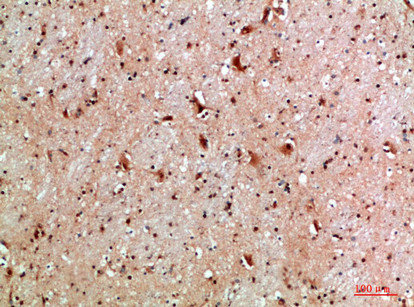

Immunohistochemical analysis of paraffin-embedded human-brain, antibody was diluted at 1:200

Immunohistochemical analysis of paraffin-embedded human-brain, antibody was diluted at 1:200